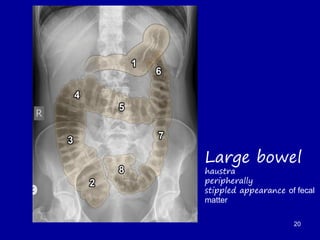

Large bowel

haustra

peripherally

stippled appearance of fecal

matter

20